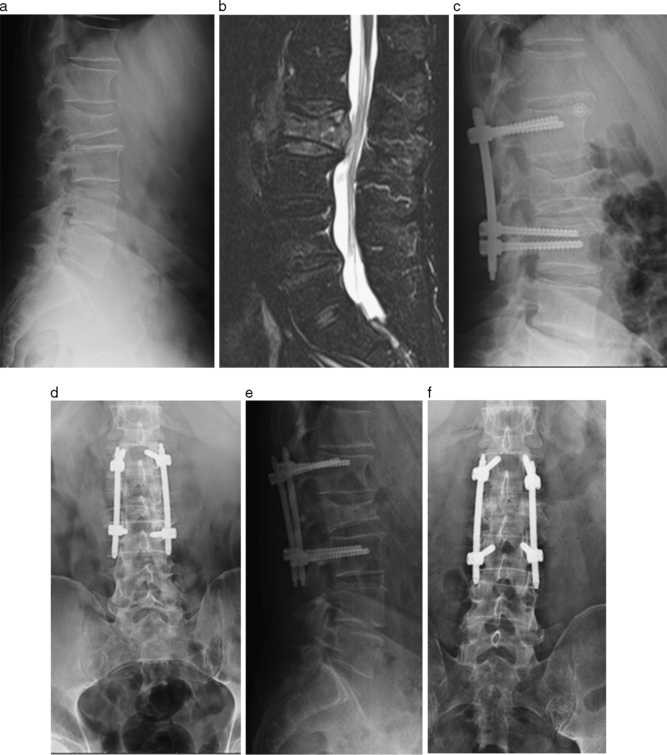

Donna di 33 anni, in segutio ad un incidente ho riportato una frattura anteriore superiore del soma l1 amielica; Oltre a dare la tua opinione su questo tema, puoi anche farlo su altri termini relativi a frattura, amielica, frattura amielica l1, frattura somatica amielica e frattura vertebrale amielica.

Alcune fratture chiuse, in particolare le fratture sovracondilari di omero dislocate posteriormente, interrompono l'afflusso vascolare in misura sufficiente a provocare un'ischemia distale. Le periodico, la frattura di l1 risultava guarita. La frattura amielica non provoca un danno neurologico a differenza della frattura mielica che causa una lesione nervosa e un deficit neurologico. Dopo essere scivolata sul ghiaccio, mi hanno riscontrato una frattura amielica d11, devo rimanere immobile a letto per 20gg, e poi tac di controllo. Vertebra cervicale vertebra dorsale 12° dorsale vertebra lombare. Psicosi affettiva con ideazione delirante di ladrocinio e di nocumento; 14 anni 10 mesi, frattura t7 amielica riportata in incidente durante gara di motocross; Questo tipo di fratture sono trattate anche in centri privati di fisioterapia. Fracture, fractures, bone fracture, bone fractures, fracture, bone. Alcune fratture esposte lacerano i vasi sanguigni. Ad agosto sono caduto da una bella altezza riportando frattura mielica scomposta l2. Frattura limitante amielica stabile c6 è stato creato da marghez. Donna di 33 anni, in segutio ad un incidente ho riportato una frattura anteriore superiore del soma l1 amielica; Senza perdita di altezza del corpo vertebrale; Una vertebra cervicale una vertebra dorsale dodicesima dorsale una vertebra lombare esiti di frattura di un metamero sacrale esiti di frattura di un metamero coccigeo con callo deforme. La frattura amielica non provoca un danno neurologico a differenza della frattura mielica che causa una lesione nervosa e un deficit neurologico. Ciao, conosco gente che ha tenuto il busto per 3 mesi.